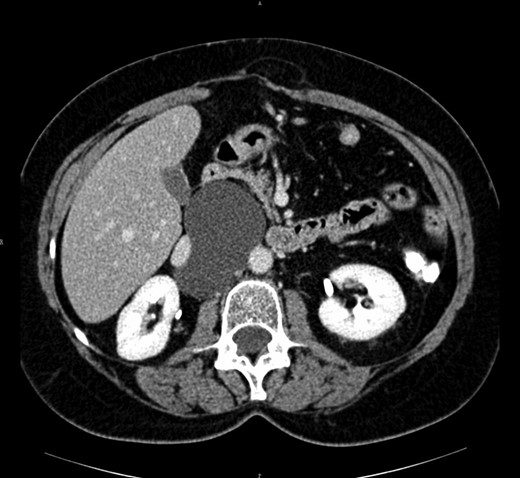

A 30 year-old man presented with diffuse abdominal pain in the last 6 months, without other abdominal or systemic symptoms. At the physical examination, a rounded swelling in the upper left quadrant was appreciated. The abdominal ultrasonography confirmed a rounded cystic formation, with regular walls, in the mesogastric region. A computed tomography scan showed a cystic mass measuring 95 × 60 mm, interjected between jejunal loops and located close to the inferior mesenteric artery and aorta (see Fig. 1).

The abdominal computed tomography scan with contrast revealed a huge (10 cm of diameter) retroperitoneal cyst, oval shaped and containing dense fluid, located within the caval vein and the aorta, under the origin of the renal artery, partially dislocating the caval vein to the right (see Fig. 2).

Computed tomography view of the mesenteric cyst partially dislocating the caval vein.